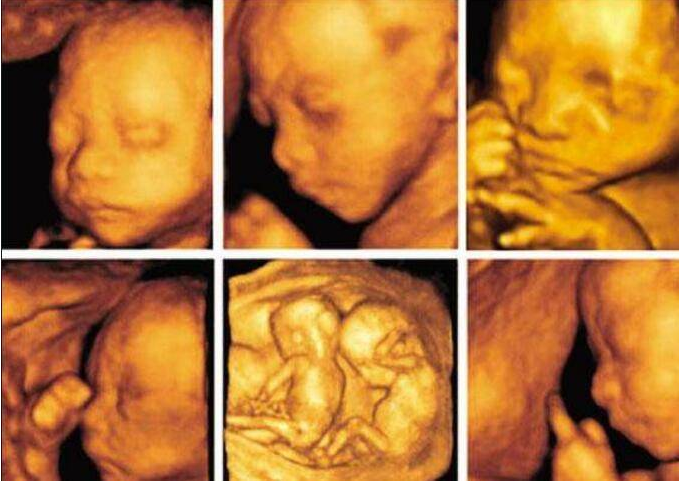

四维彩超其实就是在三维的基础上增加了实时动态的效果,让孕妇可以亲眼看到胎儿在子宫内的状况,所以很多人愿意都做四维。那么,怀孕后多久可以做四维呢?下面是晋城现代妇科医院的介绍。

一般来说,怀孕10周以上都可以做四维,但是最佳时间却是在怀孕20-28周之间,因为最合适的时间因人而异,所以这里我说的范围比较大,一般24周左右做四维就很好。因为这个时候正好是胎儿大脑进入到发育的一个阶段,胎儿的结构已经在这个时期形成,胎儿的大小和羊水适中,子宫内的运动空间较大,对胎儿骨回声的影响是比较小,图像比较清晰。